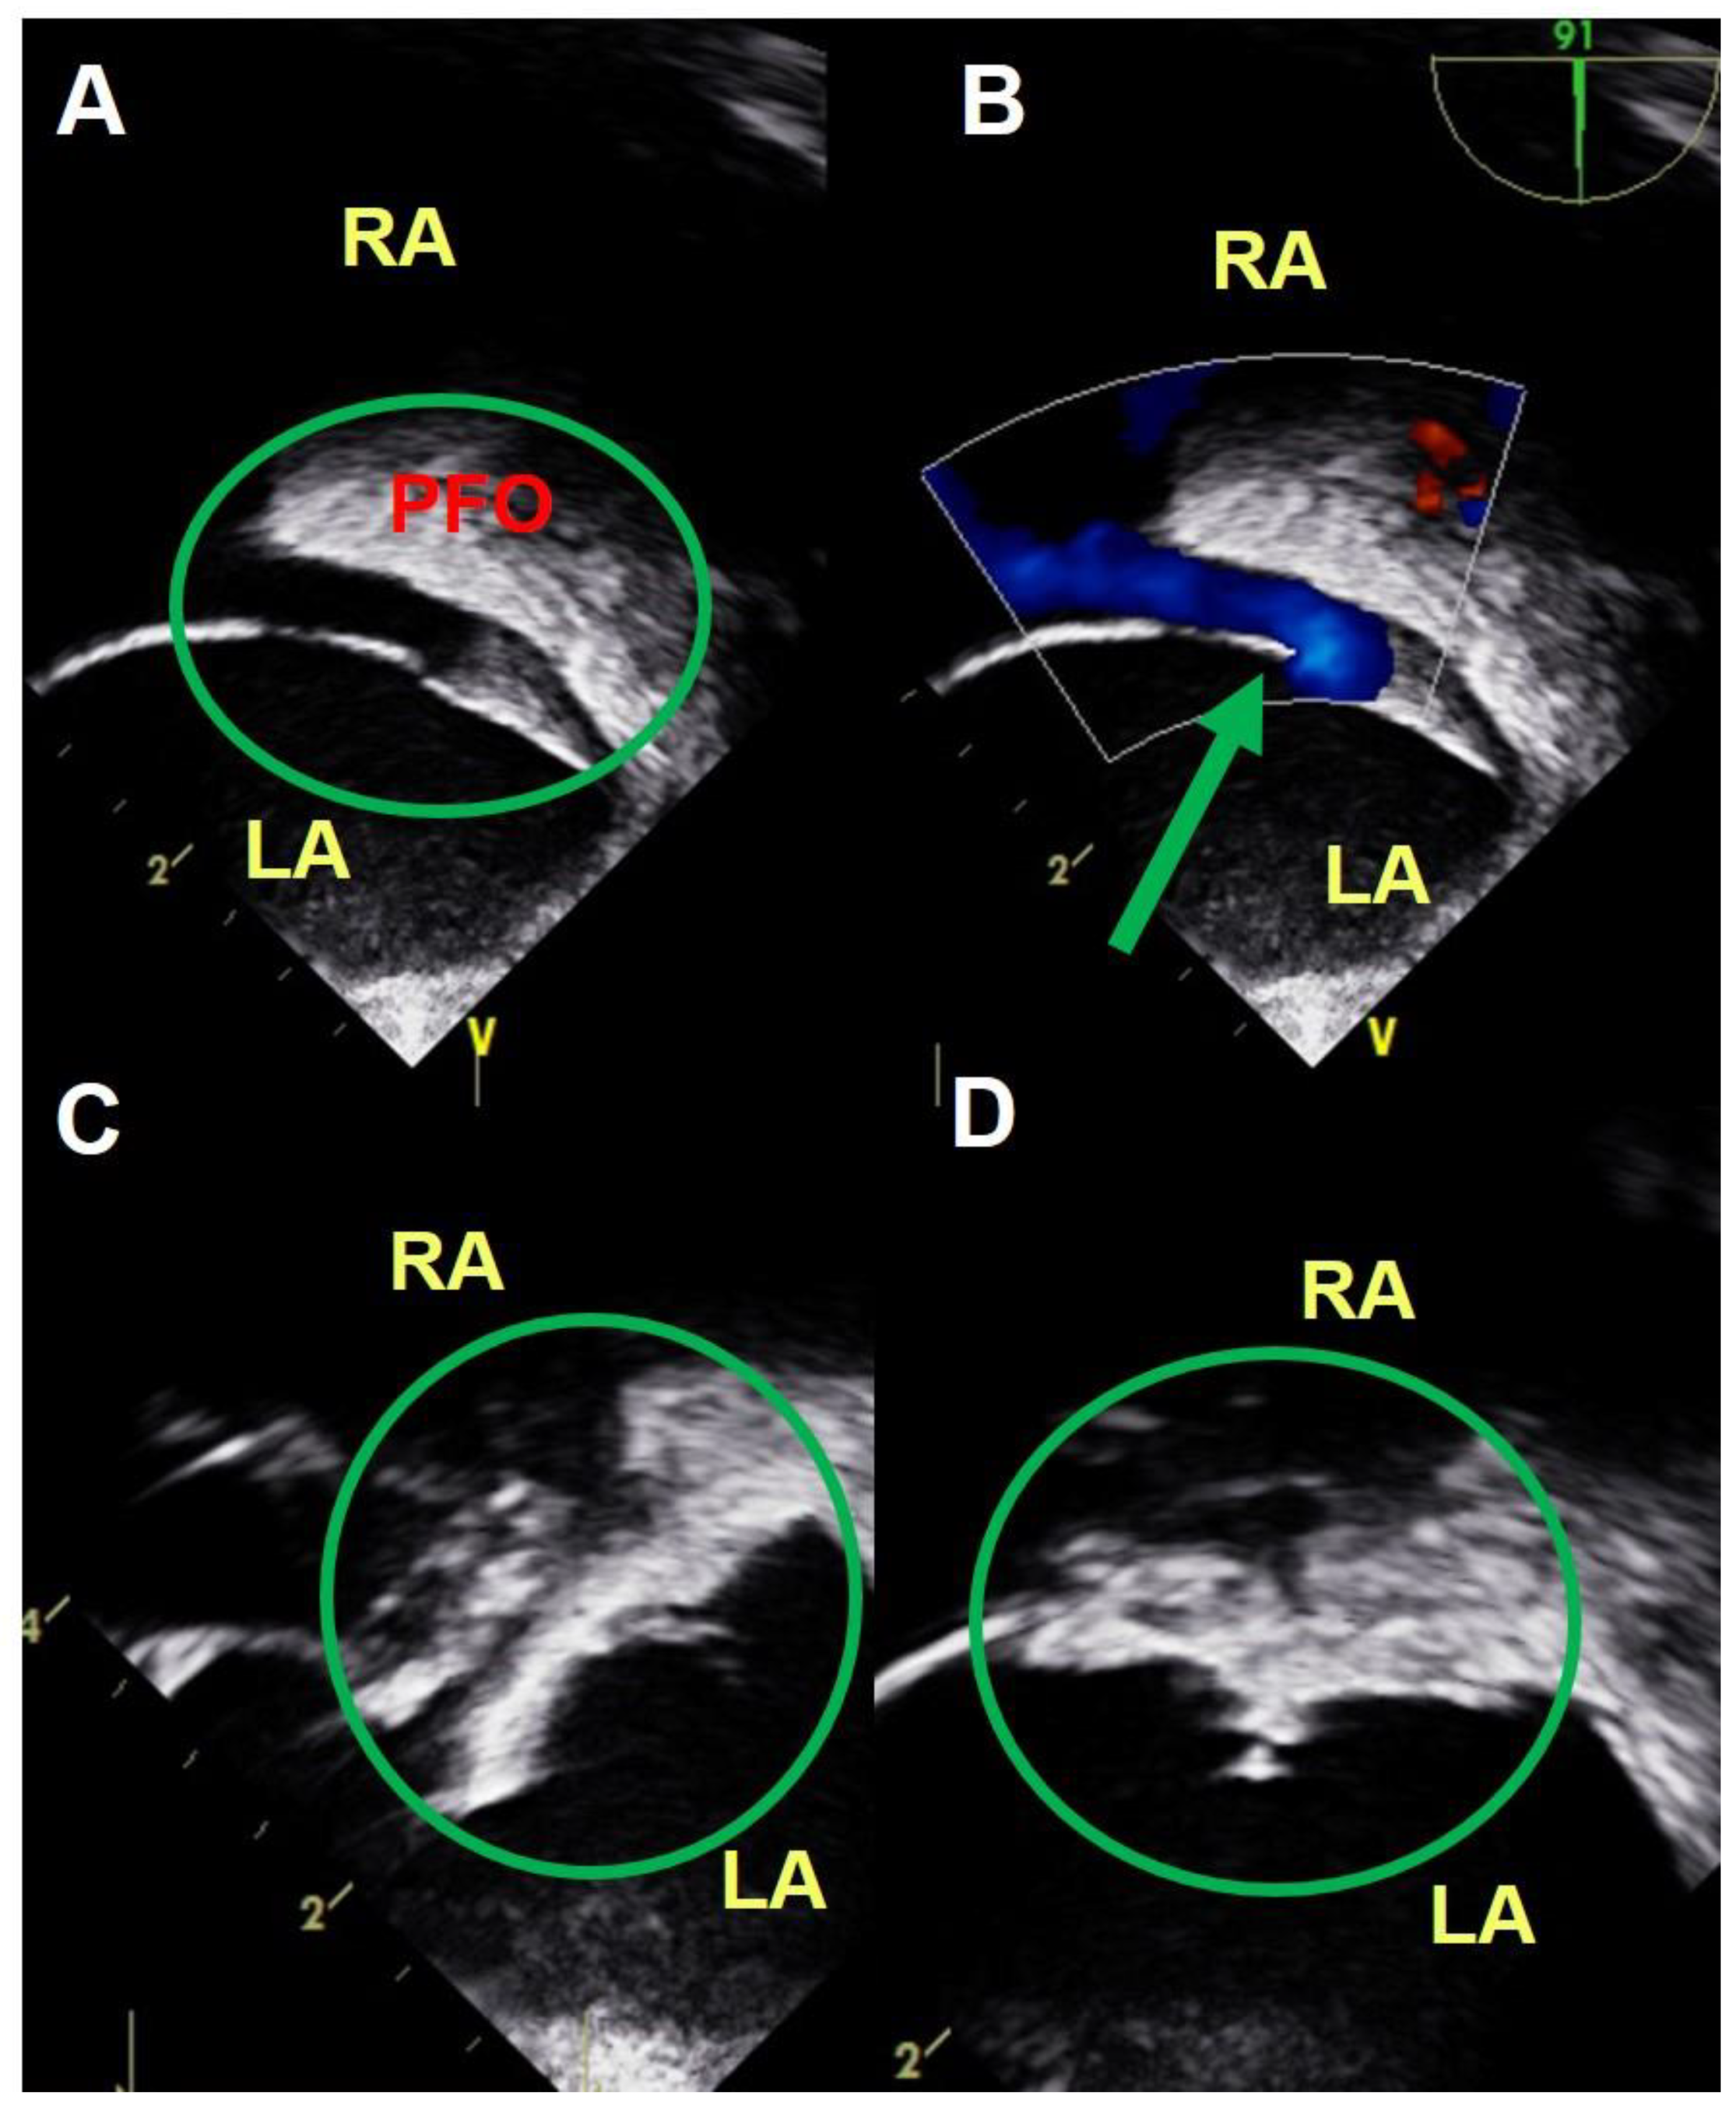

2.2. Assessment of PFO Shunt Grade and Presence of an Atrial Septal Aneurysm (ASA)

2.3. TEE Guided PFO Closure Procedure

2.4. ICE Guided PFO Closure Procedure